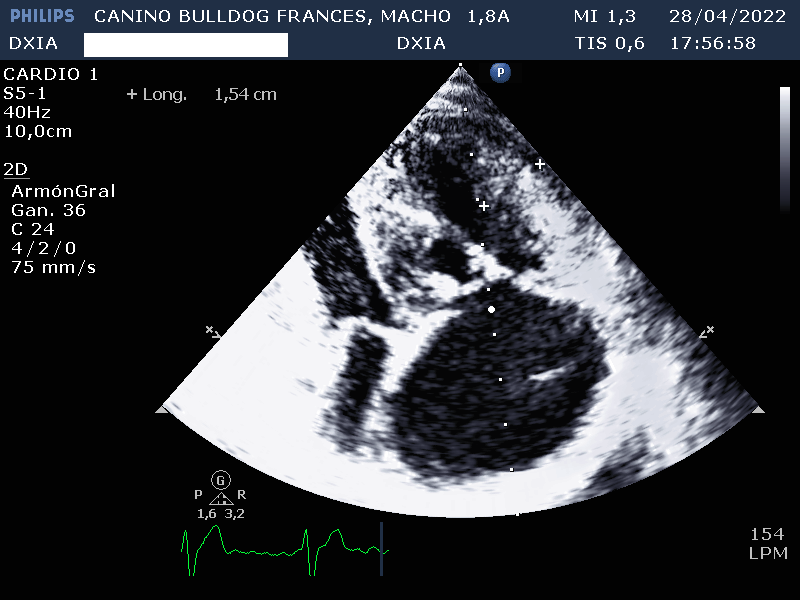

- Valvúla pulmonar: normoimplantada. Engrosamiento valvular con separación incompleta de las comisuras y dilatación post estenótica del tronco pulmonar. Gradiente de presión compatible con estenosis pulmonar severa. Movimiento paradójico del septo interventricular.

- Válvula tricúspide: Displasia de sus valvas con dilatación severá de AD. Marcado aumento e hipertrofia concéntrica de las paredes del ventrículo derecho.

Por lo tanto el estudio ecocardiográfico es compatible con posible soplo de grado IV en el lado de derecho y displasia de la válvula tricúspide con dilatación severa de AD y VD. Además, presenta estenosis pulmonar severa con leve hipertrofia de la pared del VD.